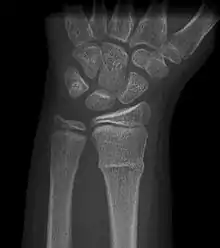

A Torus fracture, also known as a buckle fracture is the most common fracture in children.[1] It is a common occurrence following a fall, as the wrist absorbs most of the impact and compresses the bony cortex on one side and remains intact on the other, creating a bulging effect.[2] As the bulge is only on one side of the bone, this injury is can be classified as an incomplete fracture. The compressive force is provided by the trabeculae and is longitudinal to the axis of the long bone.[3] The word "torus" originates from the Latin word "protuberance."[4]

Buckle fracturs can be identified by performing a radiograph. The diagnosis of a torus fracture is made from both anterior/posterior and lateral projections. The typical features include:

- The buckling of cortical bone, which may appear as a small bulge or protuberance in the radius or ulna.

- The bone may have a slight angulation.[8]